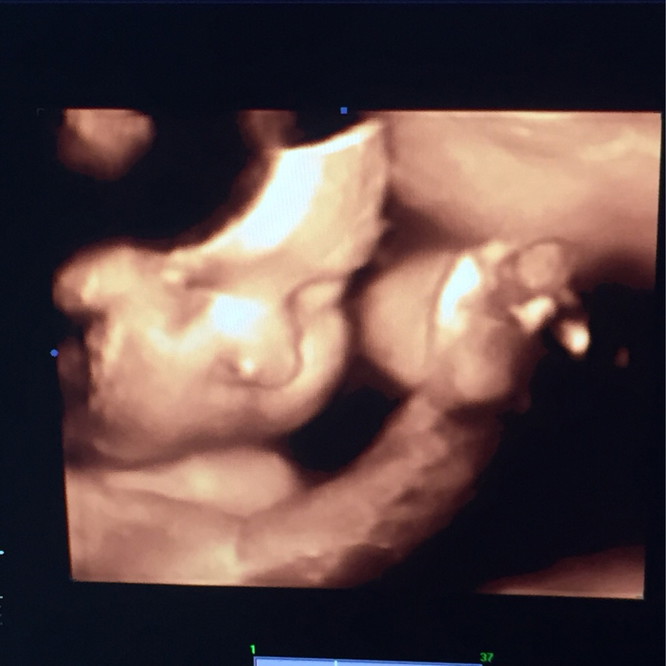

37+2 แล้วครับ